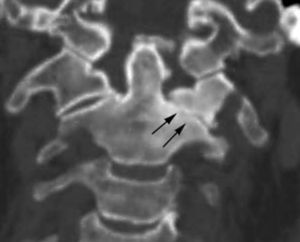

Tomografía computarizada multidetectorEl desarrollo de las nuevas técnicas de tomografía computarizada multidetector (TCMD) han permitido la adquisición de volúmenes isotrópicos que permiten reconstrucciones volumétricas y multiplanares con igual resolución en todos los planos. Su papel en el estudio de la patología degenerativa se ha incrementado de forma significativa debido a su gran resolución espacial, permite valorar el componente óseo osteofitario y la calcificación del LLP, así como la valoración del compromiso del agujero de conjunción. En algunos centros y cada vez más se considera una herramienta útil de forma prequirúrgica complementaria a la RM (fig. 3)10.

Estenosis foraminalLa RM es el método aceptado para valorar lesiones medulares; sin embargo, su resolución es menor en la valoración del componente óseo. La estenosis foraminal puede estar causada por osteofitos o herniaciones discales laterales. La precisión para valorar la causa de estrechamiento foraminal se ha visto que es menor con RM que con TCMD, aunque los planos en orientación oblicua pueden ser de utilidad. Se debe al tamaño del agujero de conjunción, al grosor de corte, a osteofitos que ocultan hernias discales y a la intensidad de señal similar del anillo fibroso, la dura y el hueso32,33.

Aunque la cirugía de la estenosis foraminal a menudo no suele estar indicada, su detección es importante para explicar los síntomas del paciente. El manejo quirúrgico cambia cuando existe una afectación foraminal asociada a una hernia discal.